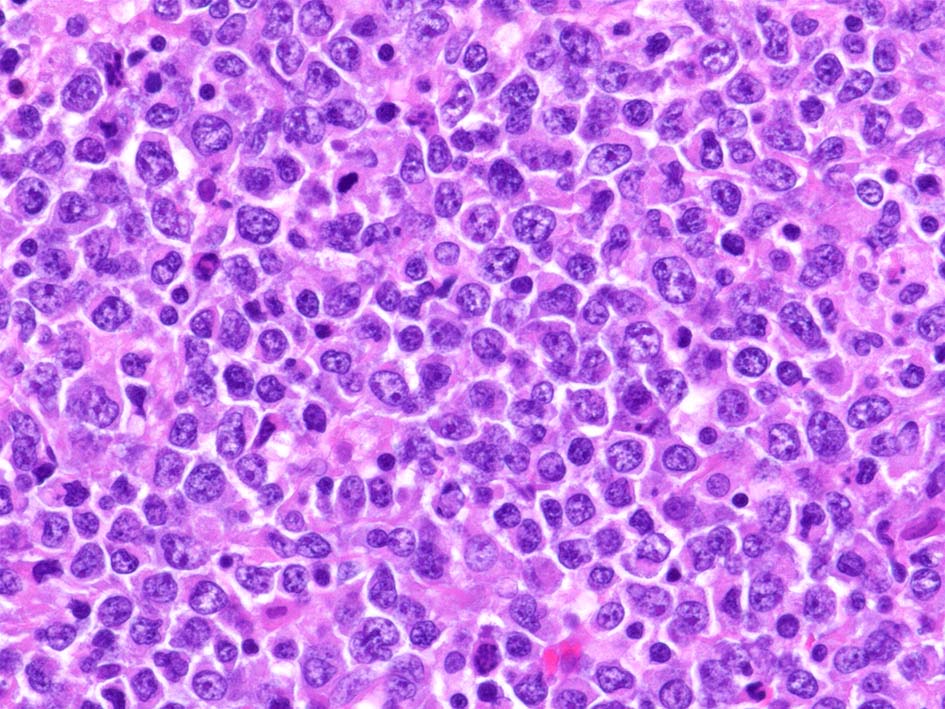

小リンパ球と同程度か1.5倍くらいのサイズ, round/ convoluted nucleiをもつリンパ球がシート状密に増殖する. 核クロマチンは粗で, 核小体が認められる核もある.

DLBCLとは細胞の大きさや細胞所見が異なっている. 精細管への浸潤, 占拠所見がある.